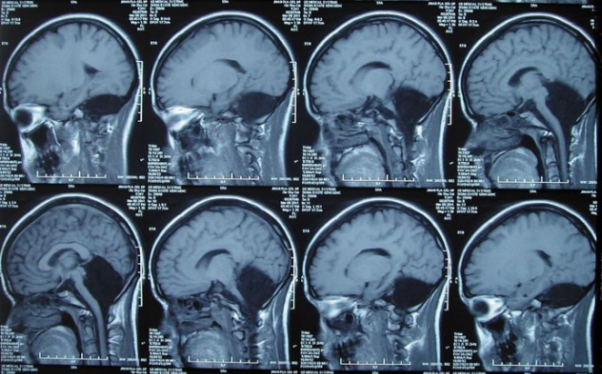

снимка от открити източници